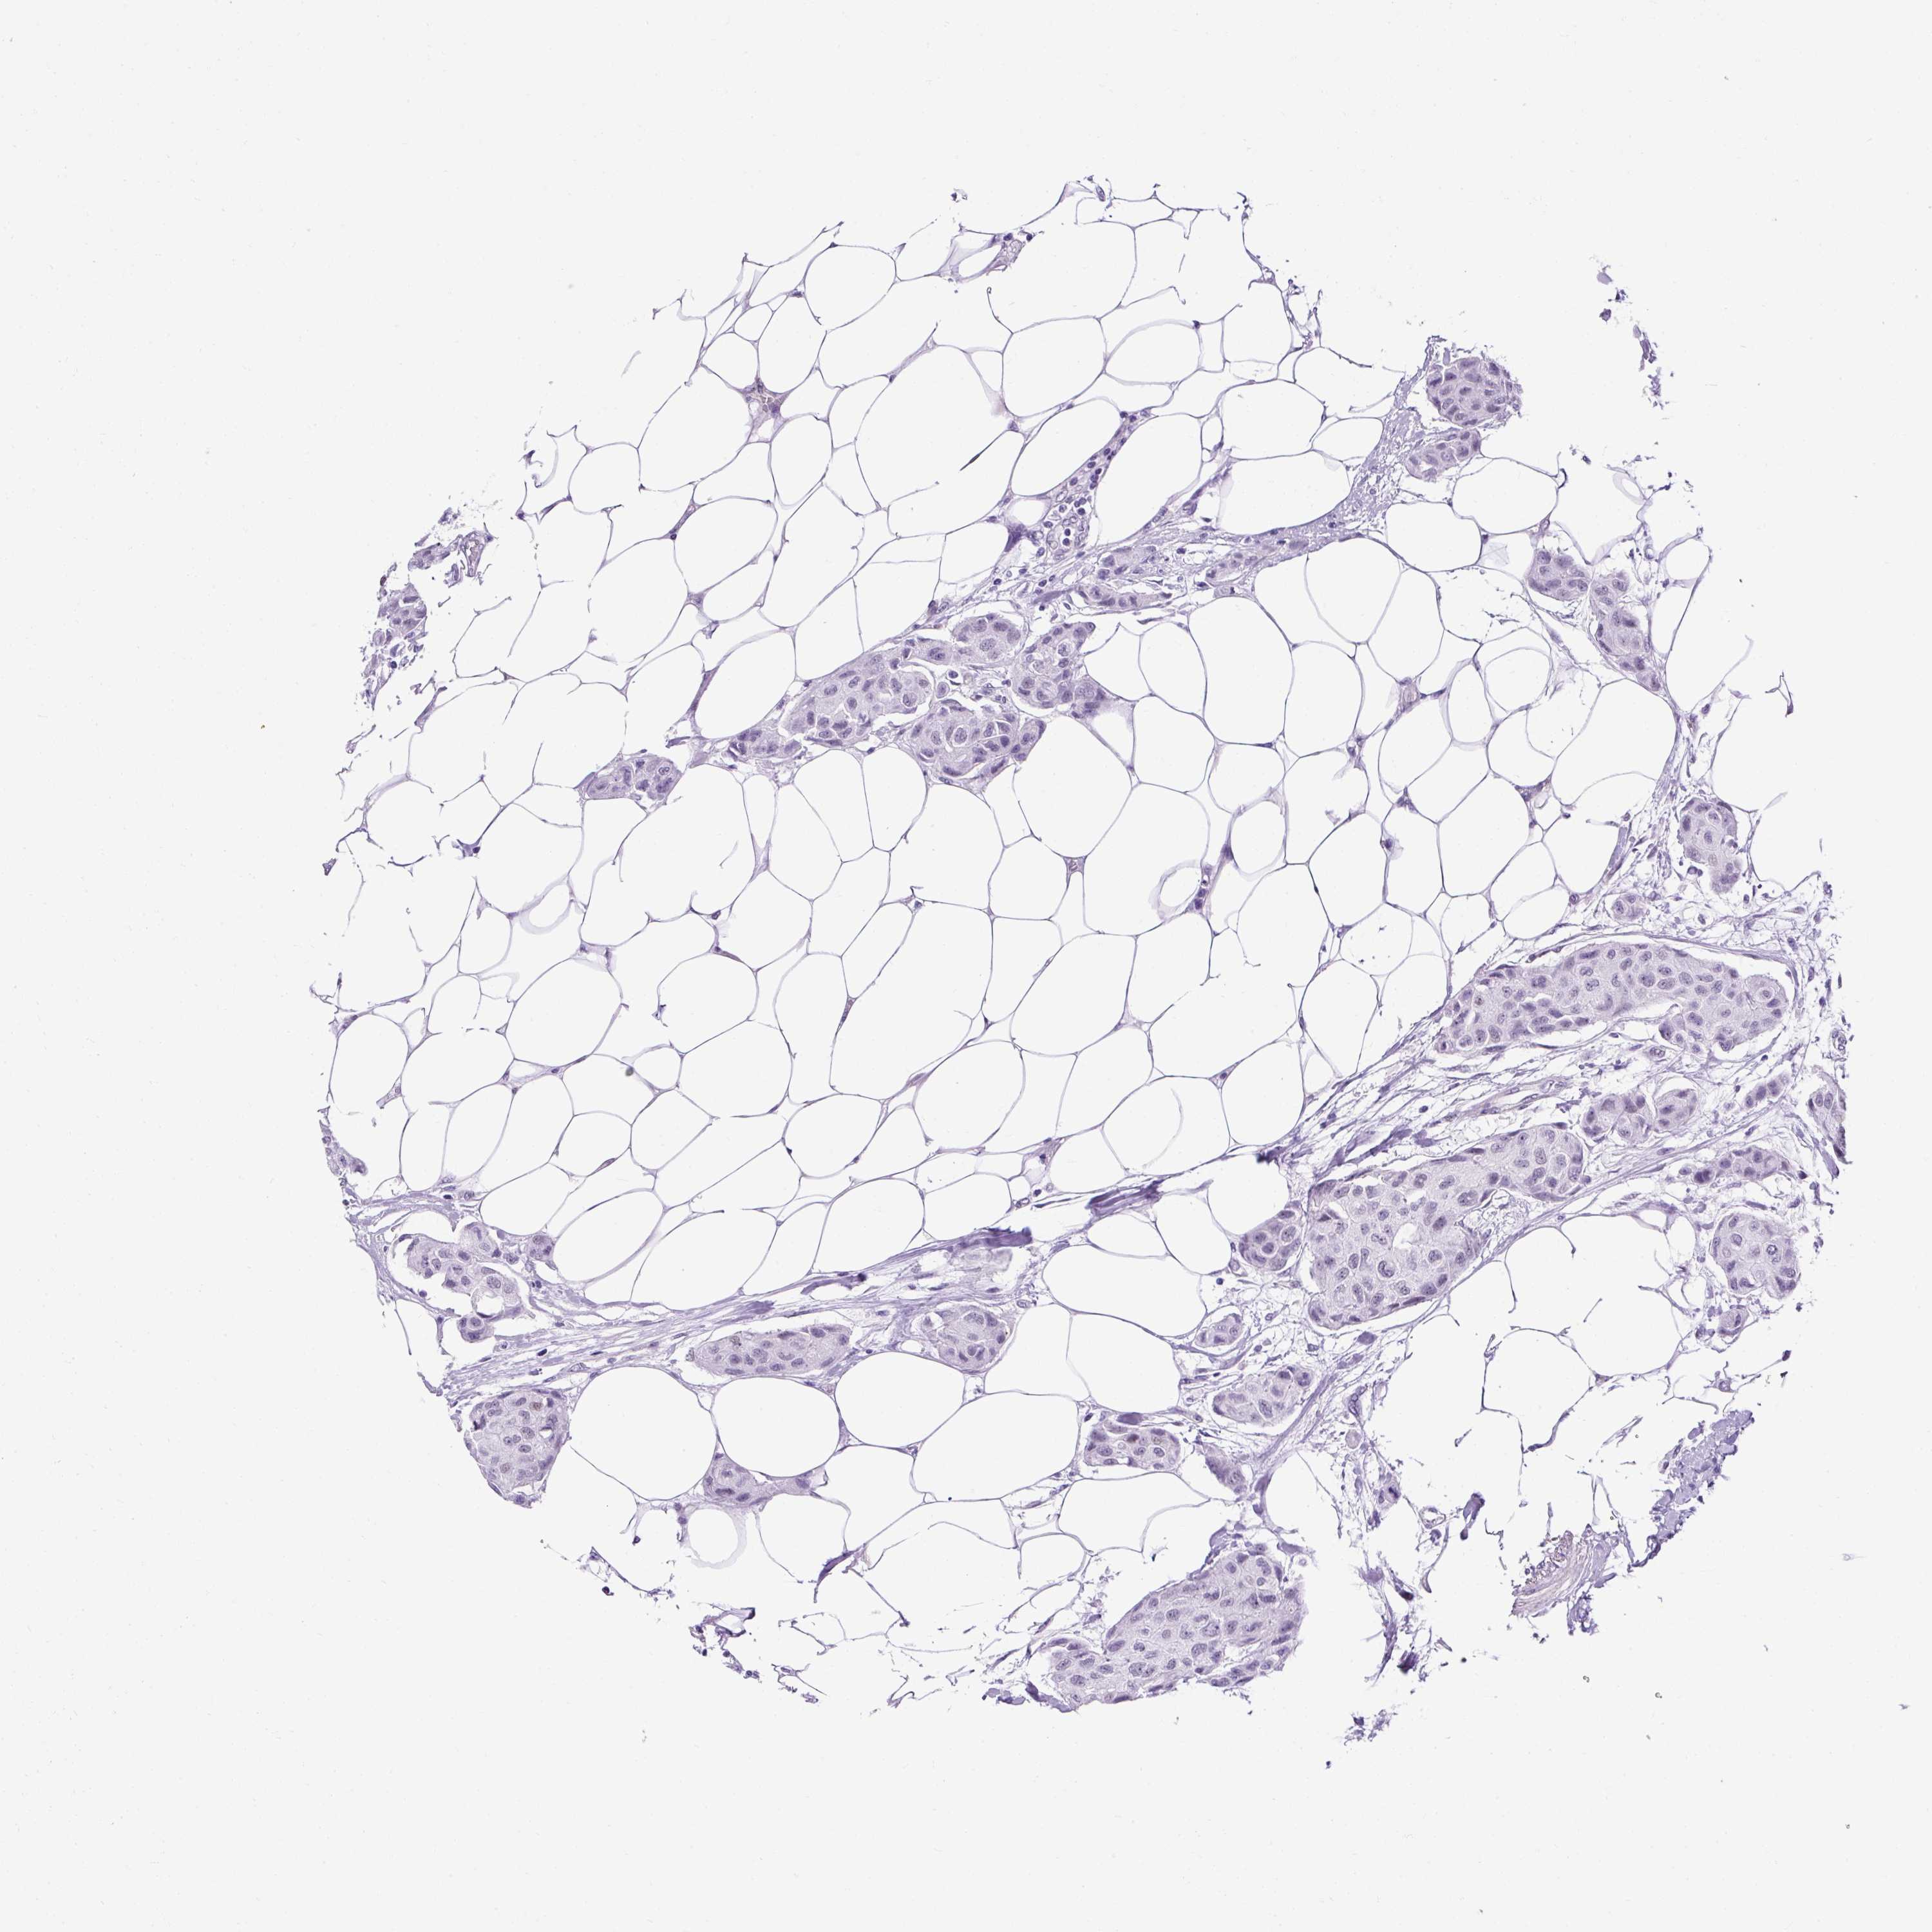

CANCER BREAST CANCER Show tissue menu

Breast cancer

Human cancer